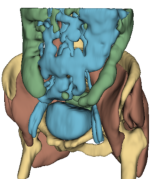

Fig. 6 presents a visual comparison of pelvic sagittal sections from different models. The model trained with L1 loss displays blurry results, with smooth intensities across the body and a noticeable lack of precise structural delineations. Conversely, the perceptual loss using MedicalNet model, while producing sharper images, tends to introduce artifacts and also falls short in defining precise anatomical structure borders. In contrast, the TotalSegmentator model delivers excellent visual quality, featuring sharp reconstruction and precise delineation of structures, notably in the colon region as depicted in the zoomed-in preview.

![]() |

| Input MR | Real CT | L1 | Perceptual | AFP TotalSeg | L1 + AFP |

| Bones | Muscles | Organs | Colon Region |

Table 6 and bottom row of Fig. 6 provide a comparative evaluation of the models on anatomical regions using the TotalSegmentator pipeline with Dice score and NSD. Aligning with the visual analysis, the model trained with the AFP loss using TotalSeg’s embeddings provide the best performances in every region. Combining the AFP loss with a L1 loss does not significantly affect the reconstruction performance of anatomical structures. The model trained with MedicalNet perceptual loss provides poor results overall, while the model trained with L1 loss delivers average performance in each region.